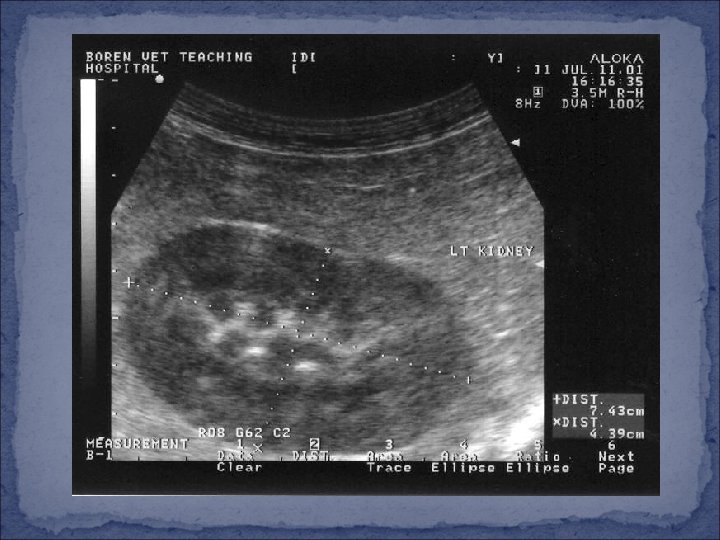

Diagnosis �Species, gender, history, clinical signs �Physical examination �Analysis of urine �IF possible…. incomplete obstruction or cystocentesis �Type of crystals/stones �Ultrasound �Urethra, bladder, kidneys, abdomen �Radiographs (x-rays) �Endoscopy